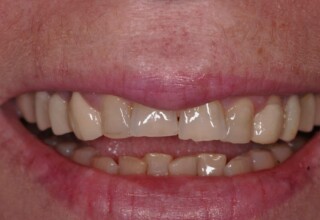

Όψεις Πορσελάνης

Οι όψεις πορσελάνης είναι ο καλύτερος τρόπος αντιμετώπισης αισθητικών προβλημάτων στην πρόσθια περιοχή του στόματος. Συνδυάζουν συντηρητική αφαίρεση οδοντικής ουσίας και πολύ υψηλή αισθητική απόδοση. Στο παρακάτω εκτεταμένο περιστατικό υπήρχαν: παλαιά σφραγίσματα, δυσχρωμίες, κακό σχήμα και μήκος δοντιών, κακή αναλογία δοντιών-ούλων. Έγινε προσεκτικός εργαστηριακός σχεδιασμός σε εκμαγεία απ’όπου προέκυψαν προσωρινές όψεις που τοποθετήθηκαν στο στόμα για δοκιμή και διορθώσεις. Όταν οριστικοποιήθηκαν οι μετατροπές, οι προσωρινές χρησιμοποιήθηκαν σαν οδηγός για τις μόνιμες. Οι πέντε μόνιμες όψεις πορσελάνης που κατασκευάστηκαν για τα πέντε πρόσθια δόντια της άνω απεκατέστησαν σχεδόν άψογα την αισθητική εμφάνιση της ασθενούς.

Αρχική εμφάνιση

Τελική εμφάνιση